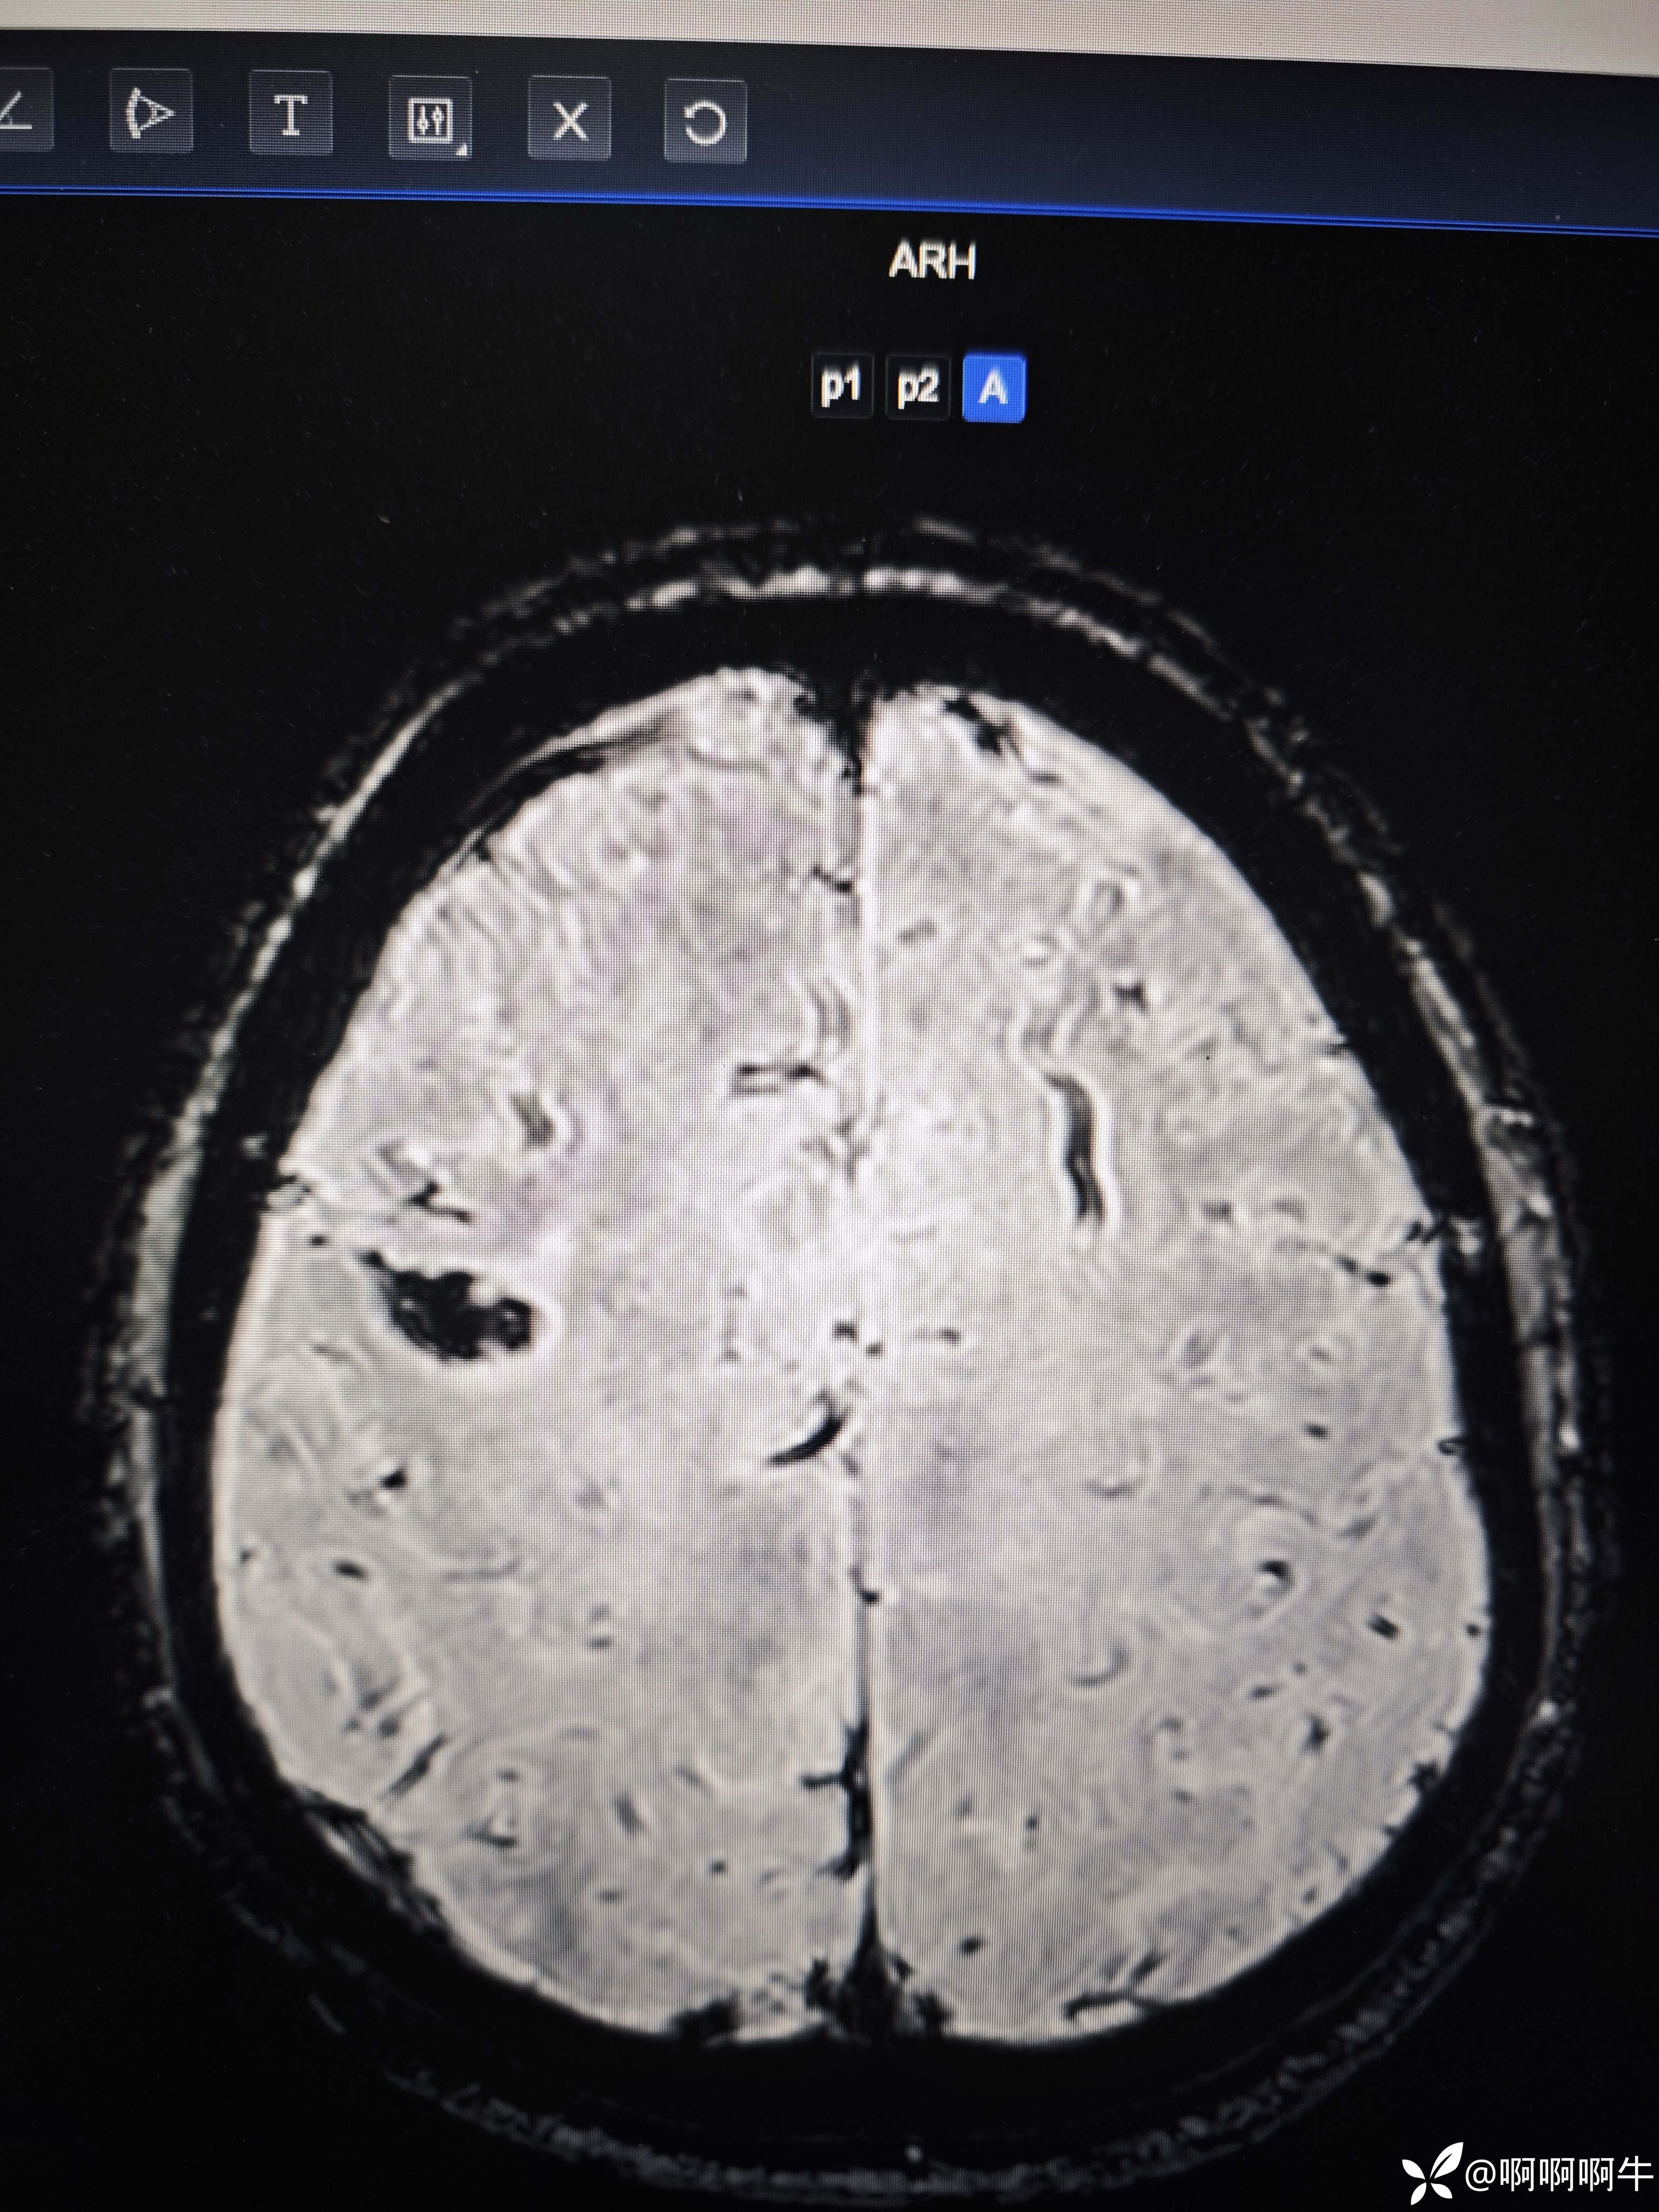

病例疑难:颅内多发病变

患者57岁,2天前因左上肢远端突发乏力体检发现颅内多发病变,目前患者无特殊不适。